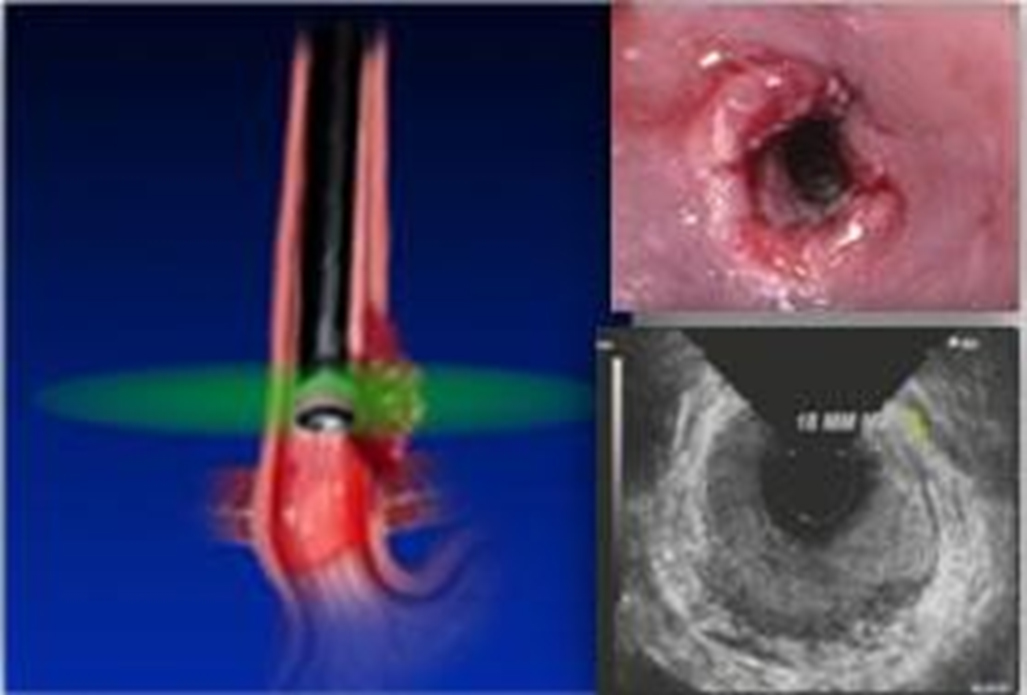

Видеогастроскоп ультразвуковой EG-UR5 (радиальный) обладает небольшим наружным диаметром, хорошими углам изгиба и широким углом поля зрения. Благодаря этому сочетанию ультразвуковое эндоскопическое исследование практически ничем не отличается от обычного эндоскопического: не вызывает дискомфорта у пациента, доктору же оставляет маневренность и удобство введения, что в свою очередь повышает эффективность такой диагностики

Одним из классических изображений ЭУС является онкология пищевода и ее взаимосвязь со стенкой пищевода. На радиальных изображениях стенка пищевода в поперечном сечении видна в виде гипоэхогенного кольца. При радиальном сканировании получается изображение, похожее на компьютерную томографию, которое легче воспринимается большинством врачей, поскольку они знакомы с методами визуализации.

Оптимальная визуализация стенки желудочно-кишечного тракта необходима для определения того, какие слои стенки вовлечены в патологический процесс.